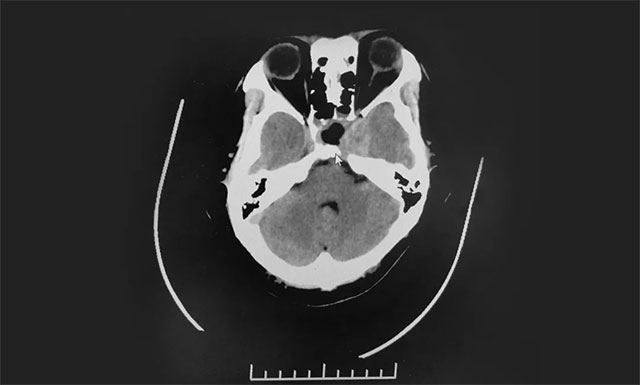

鞍區(qū)MRI平掃+增強(qiáng)顯示:蝶鞍擴(kuò)大,鞍底骨質(zhì)下陷,鞍內(nèi)垂體上緣隆起,鞍隔處見“腰癥”;增強(qiáng)掃描,病變早期和延遲期持續(xù)強(qiáng)化,最大層面約4.5*3.7*3cm;鞍上視交叉受壓上抬,左側(cè)海綿竇及左側(cè)頸內(nèi)動脈受包繞。檢查催乳素超3000μIU/mL,遠(yuǎn)超正常值。

神經(jīng)外科6B病區(qū)潘仁龍主任、李士其教授、吳治群博士會診后考慮為侵襲性泌乳素型垂體巨大腺瘤,正是垂體瘤導(dǎo)致小劉性功能下降,并且腫瘤已經(jīng)壓迫視神經(jīng)導(dǎo)致視力下降,手術(shù)指征明確。

▲ 影像顯示垂體占位,侵及左側(cè)海綿竇